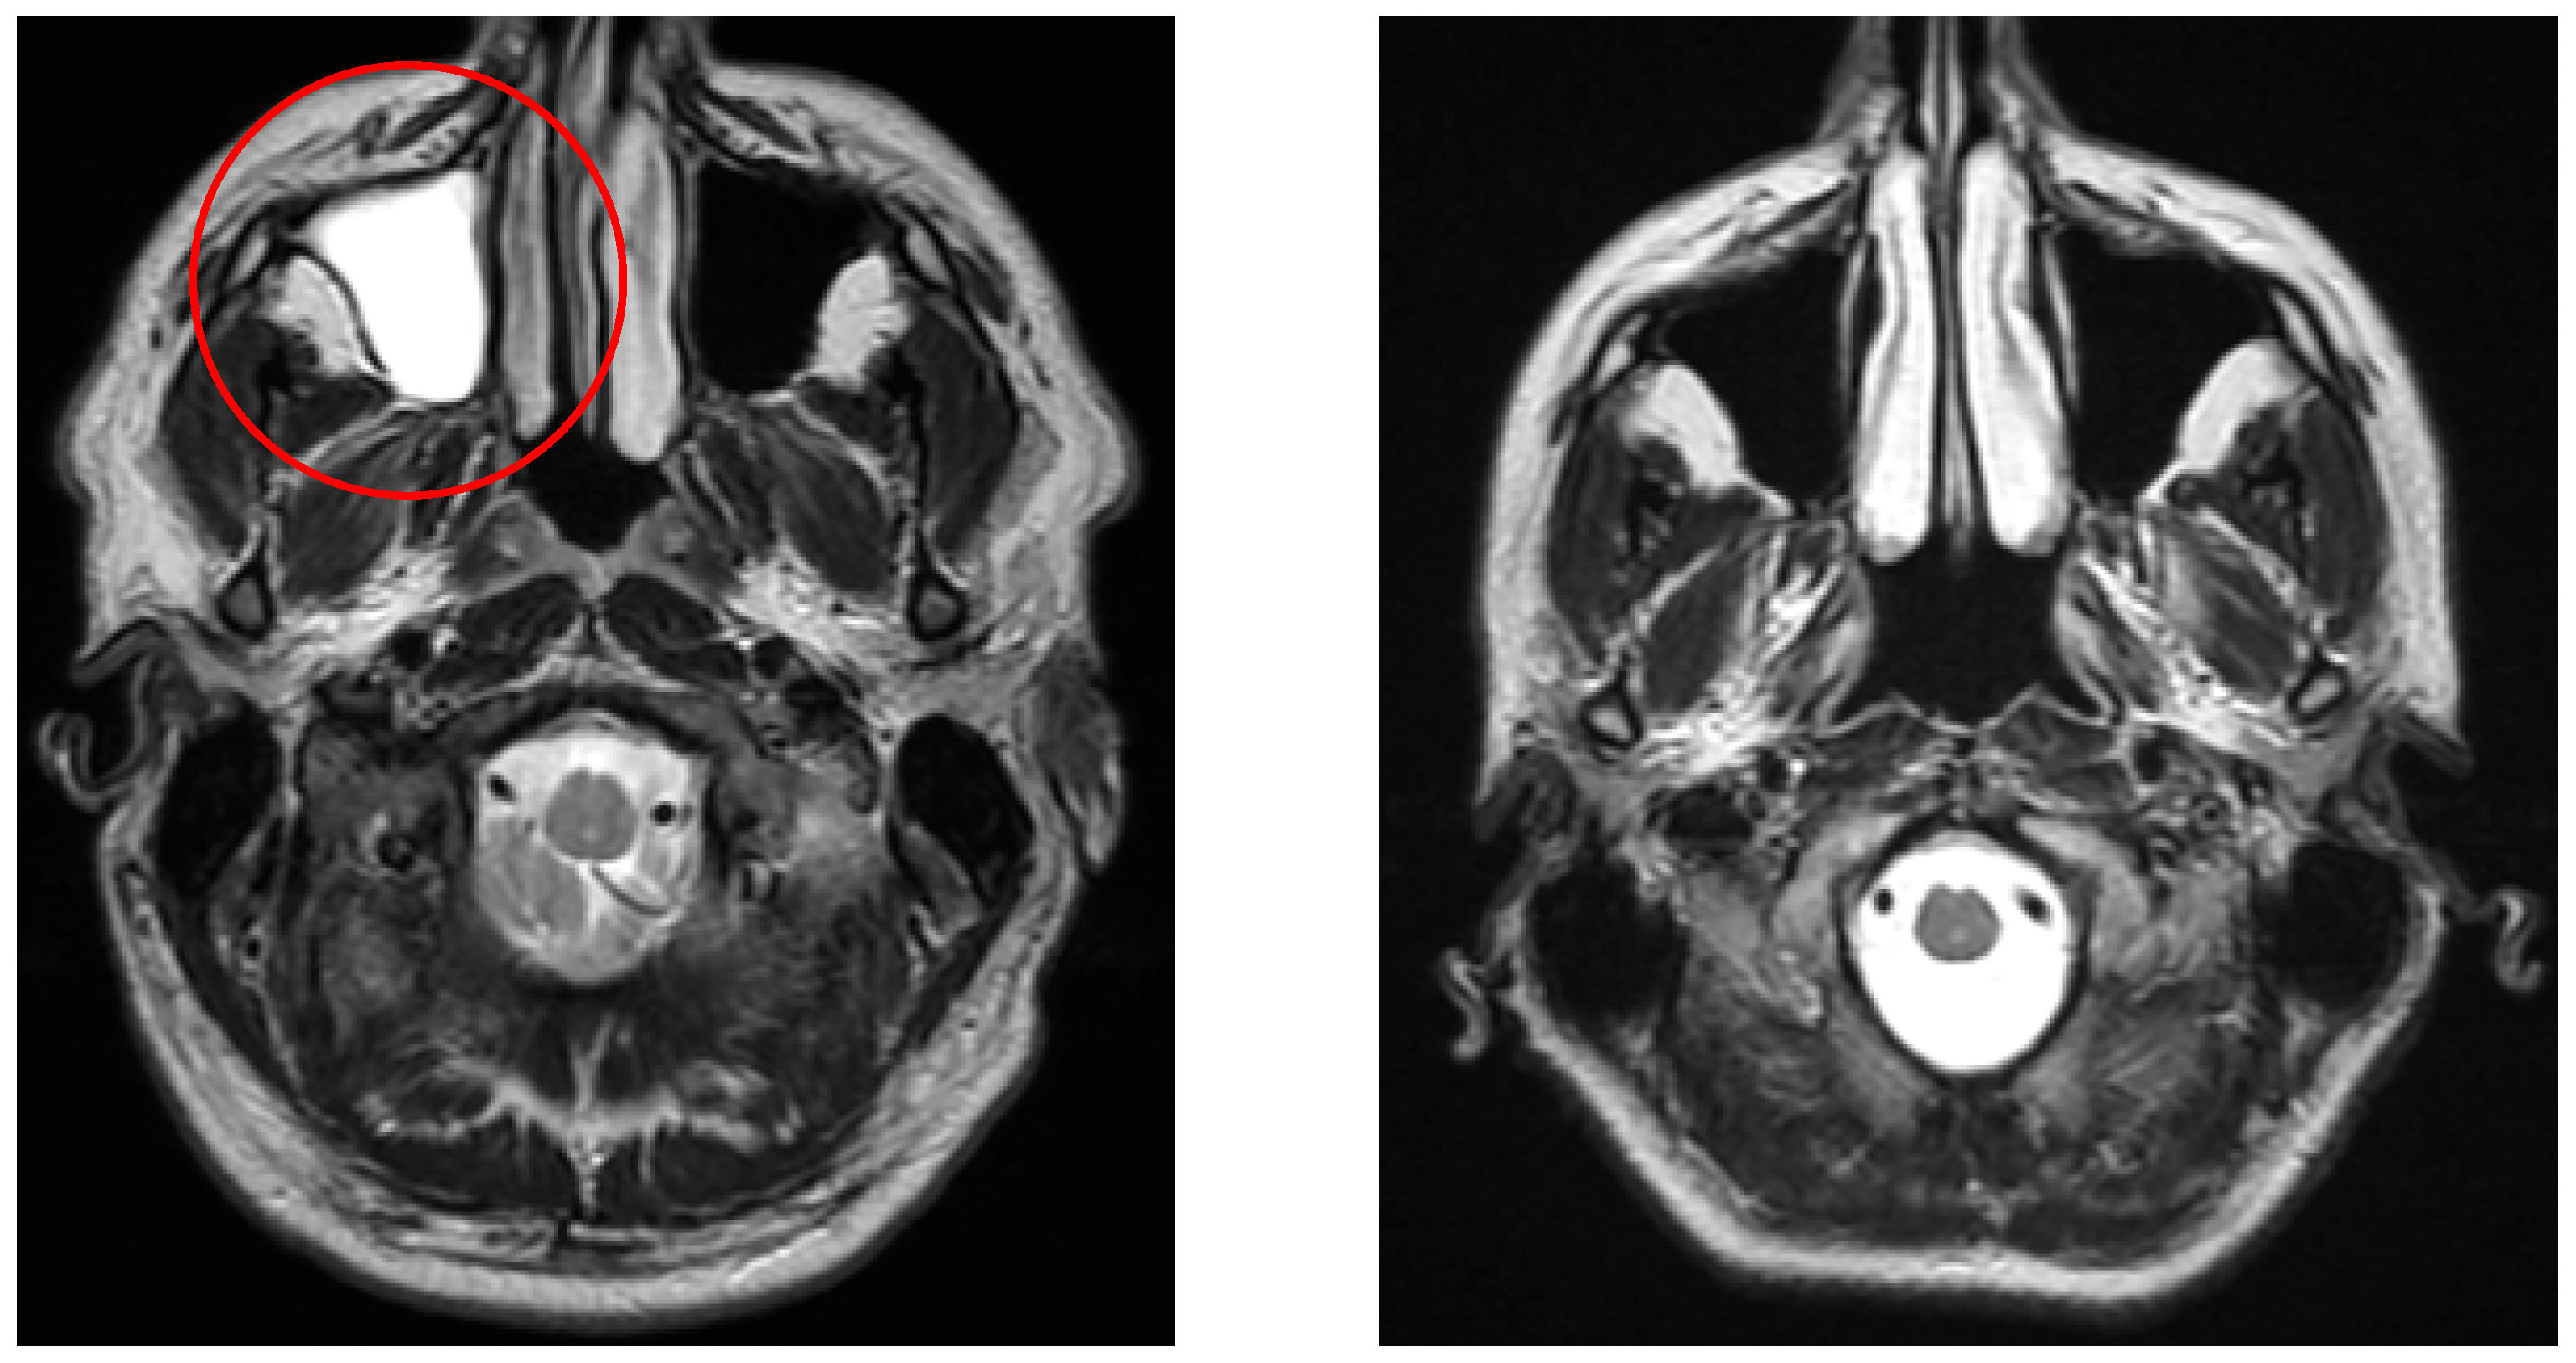

Significant differences were detected in white matter lesions (p = 0.001, see Figure 2), lacunar lesions (p = 0.047), Circle of Willis variation (p = 0.03), and sinusitis/sinus abnormalities (p = 0.005). Other MRI findings, including cortical atrophy, vascular lesion, and vascular encephalopathy, did not show statistically significant differences (p > 0.05).

Figure 3 demonstrates a typical lacunar infarct detected in the vertigo group, in contrast with controls.

Figure 2. The left image (coronal FLAIR) shows a white matter lesion (red circle) in a patient from the vertigo group, whereas the right image (coronal FLAIR) demonstrates a control patient without such lesions.